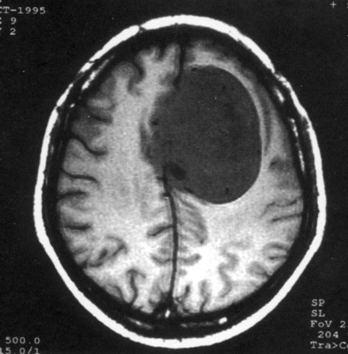

问题 病历摘要:??患者女性,37岁。大便时突起炸裂样头痛3小时,伴喷射样呕吐。既往体健。体检:T37.5℃,BP145/90mmHg,R20次/分,P85次/分。神志清楚,颅神经检查无异常,颈强直,克、布氏征(-),四肢肌力、肌张力正常,病理征(-)。 根据病史,最可能的诊断是什么?

选项 A.脑栓塞 B.脑血栓形成 C.蛛网膜下腔出血 D.脑炎 E.血管性头痛 F.脑膜炎 G.脑出血

答案 C